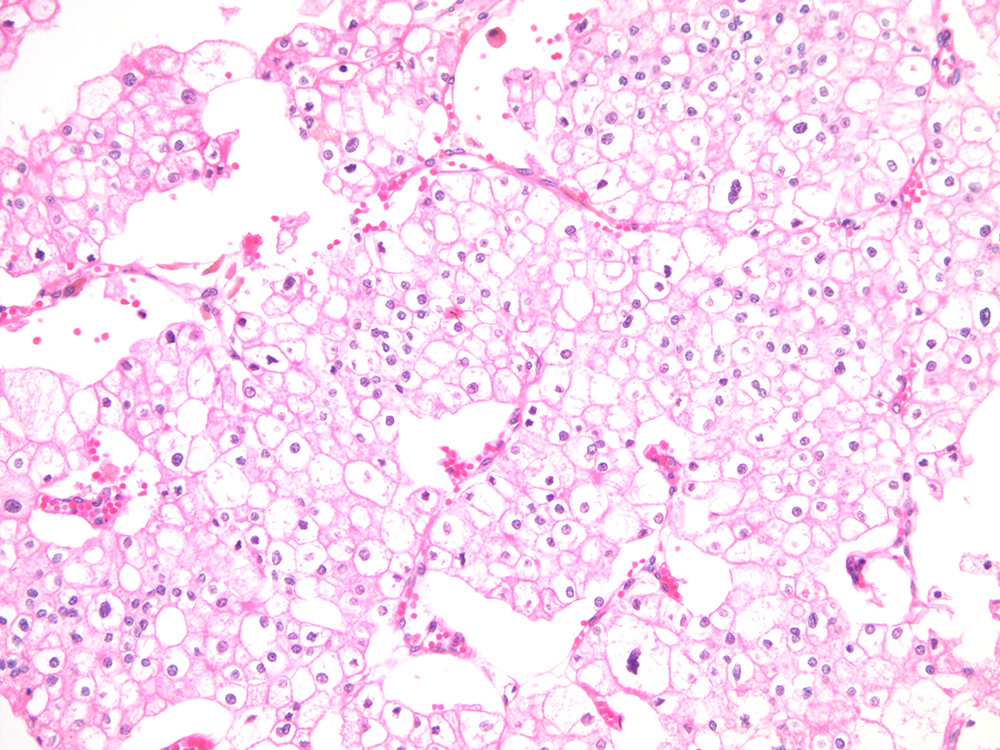

Consensus grade: I would not grade this tumor

Show diagnosis by expert panel members| User | Diagnosis | Difficulty | Comment |

| Pathologist 1 | I would not grade this tumor | Typical |

Chromophobe |

| Pathologist 2 | I would not grade this tumor | Typical | |

| Pathologist 3 | I would not grade this tumor | Typical | |

| Pathologist 4 | I would not grade this tumor | Typical | |

| Pathologist 5 | I would not grade this tumor | Typical | |

| Pathologist 6 | I would not grade this tumor | Typical | |

| Pathologist 7 | WHO/ISUP grade 1 | Borderline lower | |

| Pathologist 8 | I would not grade this tumor | Typical |

| Pathologist 18 | WHO/ISUP grade 4 | Typical |

chromophobe rcc-grading? |

Case description (by case creator):

renal mass